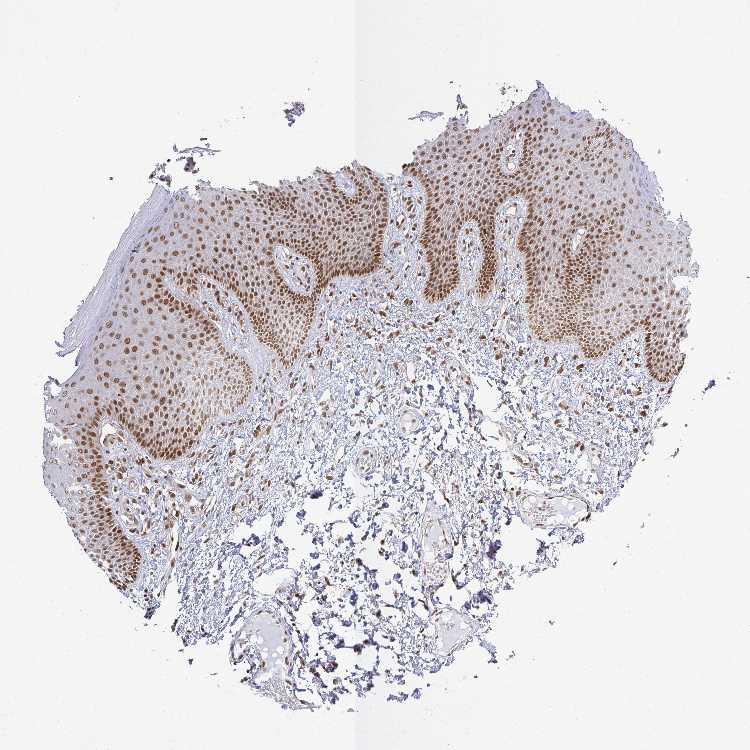

SKIN 1 - Antibody stainingi

Antibody staining in the annotated cell types in the current human tissue is reported as not detected, low, medium, or high, based on conventional immunohistochemistry profiling in selected tissues. This score is based on the combination of the staining intensity and fraction of stained cells.

Each image is clickable and will lead to virtual microscopy that enables deeper exploration of all samples and also displays staining intensity scores, fraction scores and subcellular localization as well as patient and tissue information for each sample.

Antibody HPA042933Antibody CAB010184

Langerhans HighMedium

Fibroblasts HighMedium

Keratinocytes HighLow

Melanocytes HighMedium

SKIN 2 - Antibody stainingi

Epidermal cells HighLow